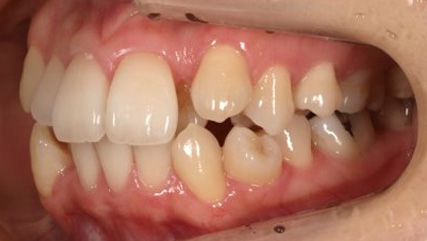

上顎前突といわれ、上顎の前歯が唇側に出ている状態を言います。

前歯が出ることで見た目の問題もありますが、口を閉じることができない、口呼吸をしてしまう、外傷などのリスクがあります。

日本人に叢生の次に多い不正咬合と言われており、自然に治ることはありません。また上の前歯が出ている事だけが気になるかもしれませんが、多くの場合、上顎の奥歯の位置に問題があることが多く、部分矯正でなく根本的な治療をした方がいい場合が殆どです。

口を閉じることができないことで、鼻呼吸でなく口呼吸をしてしまい、結果、成長期の場合顎の骨の成長を邪魔してしまうとも言われております。その他、口呼吸はアトピーなどを含むアレルギー症状の悪化、風邪を含むウイルス性の感染症にかかりやすいなどのリスクも増大してしまいます。

歯並びだけでなく全身への影響も多い為、早期の治療をおすすめ致します。